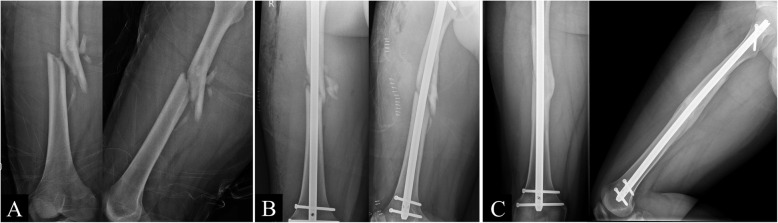

Fig. 1.

(A) Preoperative, (B) postoperative, and (C) 15-month postoperative images of a 19-year-old man with a comminuted fracture of the right femur from a motorcycle accident. Reduction and fixation were achieved via a mini-open technique, and the fracture healed 15 months after the surgery